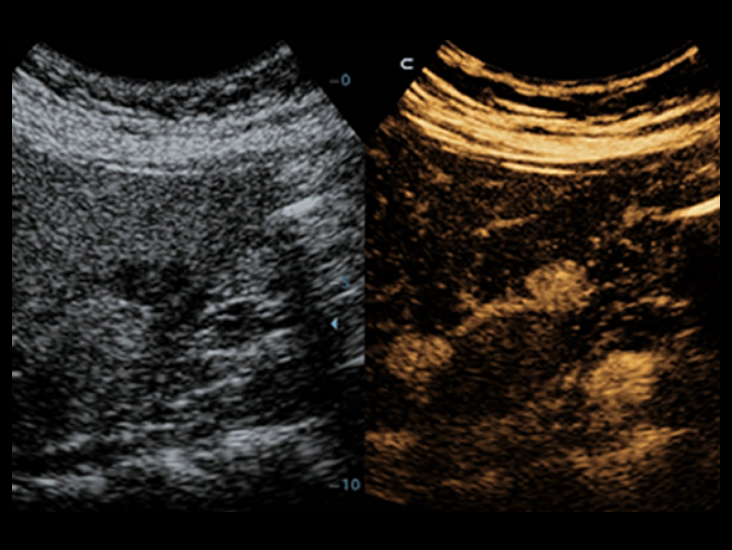

ComboWave ?????

?? ?????? ???? ComboWave ?????? ??? ??? ?? ?? ??? ???? ?? ????? ??? ????? ?? ????? ??????. ????? ??? 3T ??? ?? ??? ComboWave ??? ?????? ???? ???, ??, ?? ??? ??? ?? ???? ????? ??? ??? ??? ? ????.